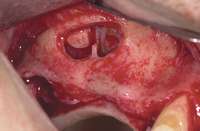

MANAGEMENT OF SINUS SEPTA

The incidence of sinus septum is 24% to 41%, with high variability in size and location; identification of the septum before the surgical sinus lift will reduce the possibility of complications.3,4 The location of the septum will dictate the size and design of the lateral wall osteotomy. The septum is isolated through careful lateral window osteotomy, defining two compartments mesial and distal to the septum. Figures 5A through Figure 5E illustrate proper management of the septum.

Figure 5A Sinus septum evident at site No. 3. Figure 5B First, the sinus septum was identified. Figure 5C Then, the septum was isolated.

Figure 5D Lastly, the septum was managed.

Figure 5E Bong graft was placed in the mesial and distal compartments.